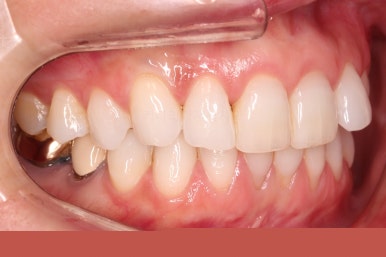

환자분이 원하시는 만큼 가지런해졌고, 부가적으로 생길 수 있는 부분들도 수용 가능한 선에서 잘 마무리가 되었습니다.

3개월이라는 빠른 기간 내에(심미보철 보다 약간만 더 긴 시간) 치아의 손상없이 마무리를 잘 했습니다.

물론 중간에 장치를 부착한 기간동안은 심미적으로 부담스러우셨겠지만요.

아래 앞니는 부분교정까지는 원하지 않으셔서 약간 다듬어 드리고 종료했습니다.